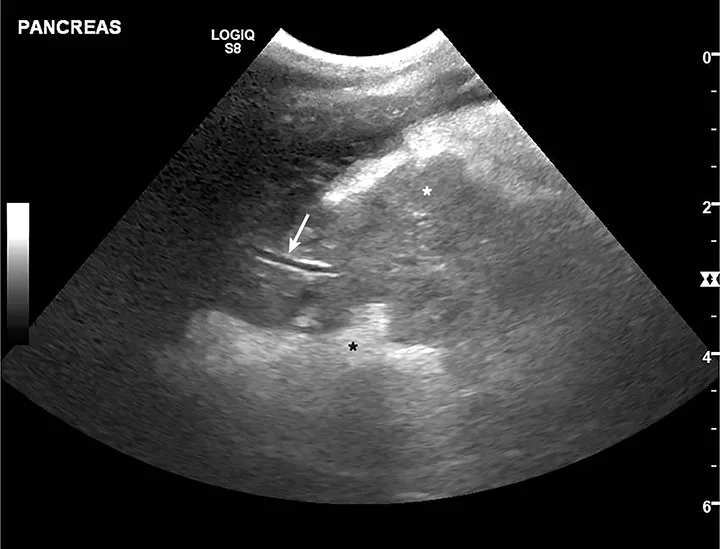

Acute pancreatitis is most frequently evaluated via abdominal ultrasonography (Figure).24-26 Findings suggestive of acute pancreatitis include pancreatic enlargement, hypoechogenicity or altered echogenicity of pancreatic parenchyma, hyperechogenicity of surrounding mesentery, and dilation of pancreatic or biliary ducts. Other nonspecific findings include ascites, gastric wall thickening, lateral displacement of the duodenum, and intestinal ileus.24-26 Discordant sensitivity and specificity of ultrasound for diagnosis of acute pancreatitis have been reported; variable results are influenced by differing case definitions for acute pancreatitis and number of ultrasound criteria used for diagnosis.7,27 Ultrasound use is also presumably related to other factors (eg, equipment quality, clinician expertise). Results from one study suggested high sensitivity and poor specificity when only 1 or 2 ultrasonographic features were required for acute pancreatitis diagnosis; poor sensitivity and high specificity were found when ≥3 features were required for diagnosis.27

Ultrasound image of the pancreas in a dog with acute pancreatitis.

FIGURE

Ultrasound image of a 10-year-old spayed fox terrier with classic acute pancreatitis findings. Pancreas is enlarged and diffusely hypoechoic (white star; pancreatic mesentery) with undulating margins. Surrounding mesentery is diffusely hyperechoic (black star; peripancreatic fat). Normal pancreatic vein (arrow) can be seen.